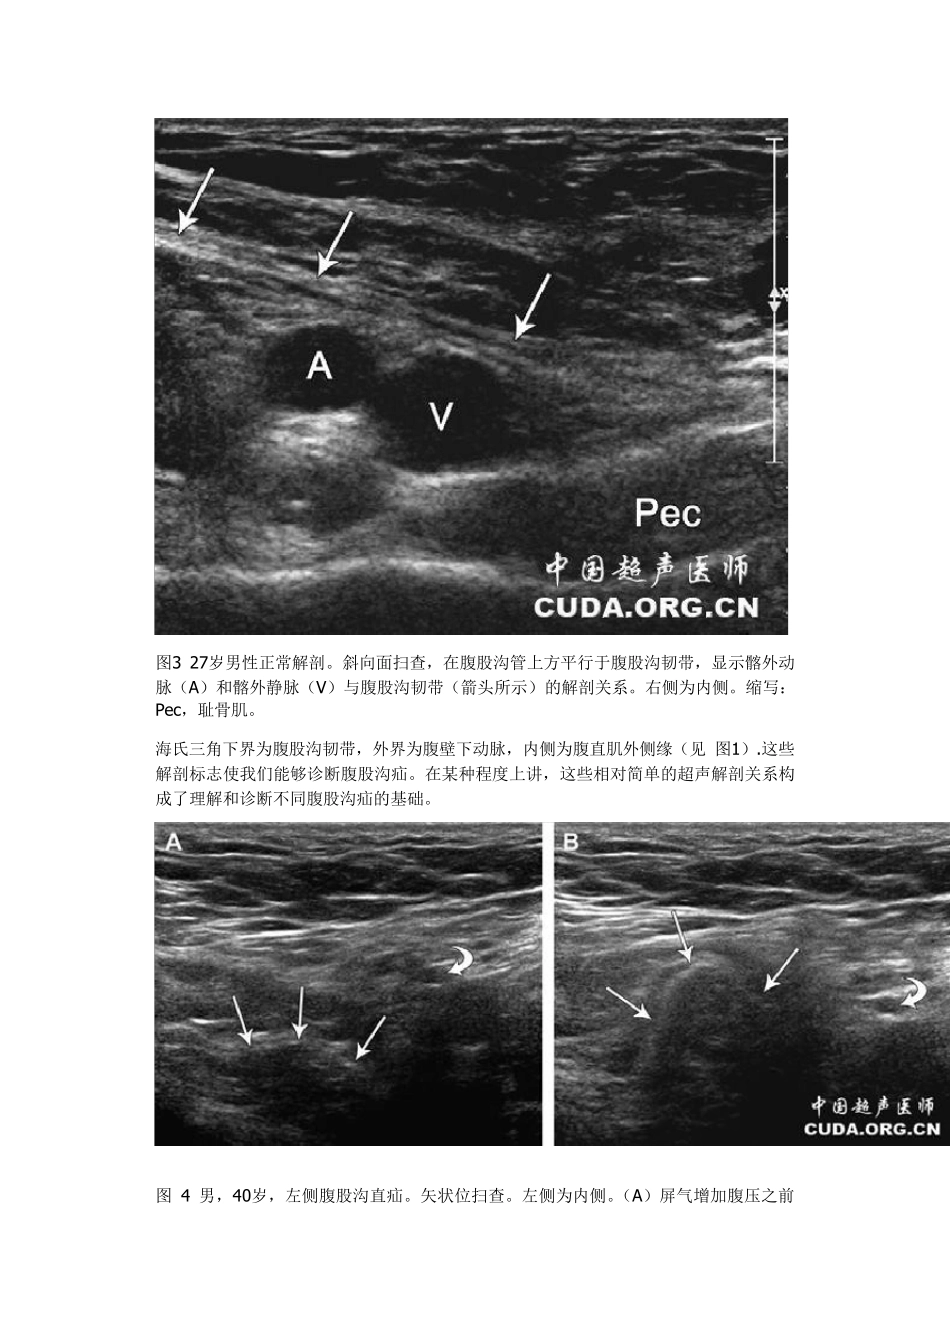

腹 股 沟 疝 的 超 声诊断 腹股沟疝是腹部最常见的疝。约25%男性患有医学意义上的腹股沟疝,而女性的发病率仅3%。然而,股疝在女性更常见。 腹股沟区的解剖:前下腹壁是精索(女性为圆韧带)和从腹腔内来的盆腔血管移行到腹腔外的地方,所以形成了复杂的机制以保护腹腔脏器。在腹股沟薄弱区域这种保护机制丧失则导致疝的发生。 腹壁下动脉和耻骨结节作为诊断和鉴别腹股沟直疝和斜疝的唯一标志。 腹壁下动脉位于腹直肌的外缘,并进入其深面。腹壁下动脉起源于髂外动脉,起源部位位于腹股沟韧带的前面,并在此跨越腹股沟韧带。这一解剖点很重要,就在其起始点的远端即是跨越髂外动脉/股动脉的腹股沟韧带。如将探头放于腹壁下动脉与耻骨结节连线上成像,可以显示构成海氏三角下缘的腹股沟韧带的内侧部分。腹股沟韧带显示致密纤维样狭窄线性结构 图1 从腹腔内所见右侧腹股沟解剖。腹直肌外侧缘(Rect),腹壁下动脉(直箭头),腹股沟韧带内侧(箭头)所界定的海氏三角(H)。腹股沟韧带起源于髂前上脊(S)并插入耻骨结节(T)。缩写:F,股管;Ram ,耻骨上支,弯箭头所示之处为腹股沟管深环的开口。 图2 27岁正常男性解剖。在腹直肌外侧缘(R)矢状位图像,此处腹壁下动脉和静脉(箭头所示)刚好穿越半月线。左面为内侧。缩写:F,腹斜肌群。 图3 27岁男性正常解剖。斜向面扫查,在腹股沟管上方平行于腹股沟韧带,显示髂外动脉(A)和髂外静脉(V)与腹股沟韧带(箭头所示)的解剖关系。右侧为内侧。缩写:Pec,耻骨肌。 海氏三角下界为腹股沟韧带,外界为腹壁下动脉,内侧为腹直肌外侧缘(见 图1).这些解剖标志使我们能够诊断腹股沟疝。在某种程度上讲,这些相对简单的超声解剖关系构成了理解和诊断不同腹股沟疝的基础。 图 4 男,40岁,左侧腹股沟直疝。矢状位扫查。左侧为内侧。(A)屏气增加腹压之前所示的腹壁下动脉(弯箭头)和腹膜脂肪纹(直箭头)。(B)屏气增加腹压(Valsava maneuver),可见直疝(直箭头),变性的腹膜反折,伴有朝向探头方向的运动。疝位于腹壁下动脉(弯箭头)的内侧。注意疝(更靠近探头)在屏气增加腹压时比腹壁下动脉更表浅。 腹股沟疝的类型取决于疝囊颈的位置。疝囊颈位于腹壁缺损的部位,疝内容物从疝囊颈突出。直疝的疝囊颈位于海氏三角内(见图1、4)。腹股沟斜疝的疝囊颈位于腹壁下动脉的外侧腹股沟韧带头侧腹股沟管深环(见图4、5、6)。股疝的疝囊颈位于腹股沟韧带尾侧股静脉...